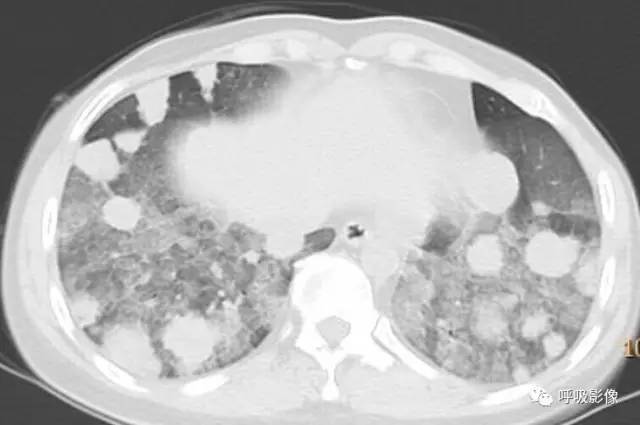

胸部CT示双肺多发结节影,强化明显,内见明显坏死,提示血供丰富。

转移瘤多具有原发肿瘤特点,本例转移瘤为生殖源性肿瘤,盆腔附件包块穿刺活检细胞学检病理均查见恶性肿瘤细胞,结合转移灶坏死、强化明显,需考虑绒毛膜癌可能。

胸部CT双肺多发结节影,强化明显,内见明显坏死,提示血供丰富,这是诊断关键。